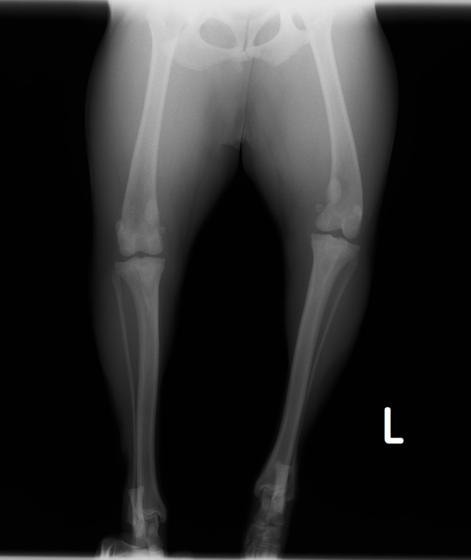

■ 症例24 キャバリア 7か月

左右膝蓋骨内方脱臼(左:グレードⅣ 右:グレードⅢ)

以前から左右後肢の跛行が認められ、整形外科学的検査・レントゲン検査により左右の膝蓋骨脱臼が認められた。症状が重度である左膝の膝蓋骨脱臼整復術を行った。外科手技は縫工筋及び内側広筋の解放、脛骨粗面の外側転位、滑車ブロック形造溝術、内外側関節方の縫縮を実施した。術後一か月時点で、左の膝蓋骨は安定しており経過は良好である。

本症例は成長期における重度の膝蓋骨脱臼であり、術後の再発の可能性もあるため、経過をしっかりと観察していく必要がある。また、今回手術を実施していない右膝に関しても経過を観察し、手術を検討していくこととする。